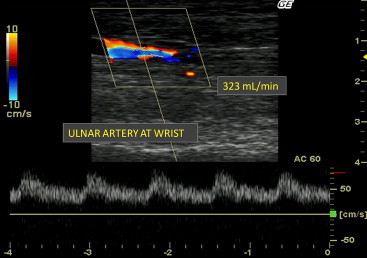

Fig. 1.

Color Doppler ultrasound: characteristics of the ulnar artery at first evaluation.

The new AVF was patent and functioned well, but the patient complained of increasingly severe, sharp pain in the left hand during dialysis. The pain was so severe that the patient was often unable to complete dialysis, and his dry weight increased considerably. For this reason, the AVF was examined with color Doppler sonography. It revealed the presence of an LT anastomosis between the pre-bifurcation segment of the BA and the MV with predominant development of the cephalic venous branch. The AVF displayed a high flow rate (about 2000 mL/min) in the BA. Flow in the radial artery (RA) distal to the anastomosis was initially retrograde. It later became orthodromic although the flow rate was only about 18 mL/min. Ulnar artery (UA) flow had the same directional characteristics, but the flow gradually increased as the transducer was advanced toward the hand, and a rate of around 323 mL/min was recorded at the wrist. It also included a significant diastolic component, which was indicative of low resistance in the distal arterial segment of the hand (Fig. 1). Careful exploration of the site of the patient’s original radio-cephalic fistula revealed the persistence of a small residual anastomosis between the RA and cephalic vein (CV). Flow through this fistula came from the UA (via the palmar arch), and the rate was about 300 mL/min. This finding was confirmed by the presence of an audible thrill over the radio-cephalic AVF. The concomitant presence of two functioning vascular accesses on the same arm – a distal, radio-cephalic fistula with limited flow (about 300 mL/min) and a proximal brachio-median fistula with high flow (about 2000 mL/min) – was thus identified as the cause of symptoms of hypoperfusion.